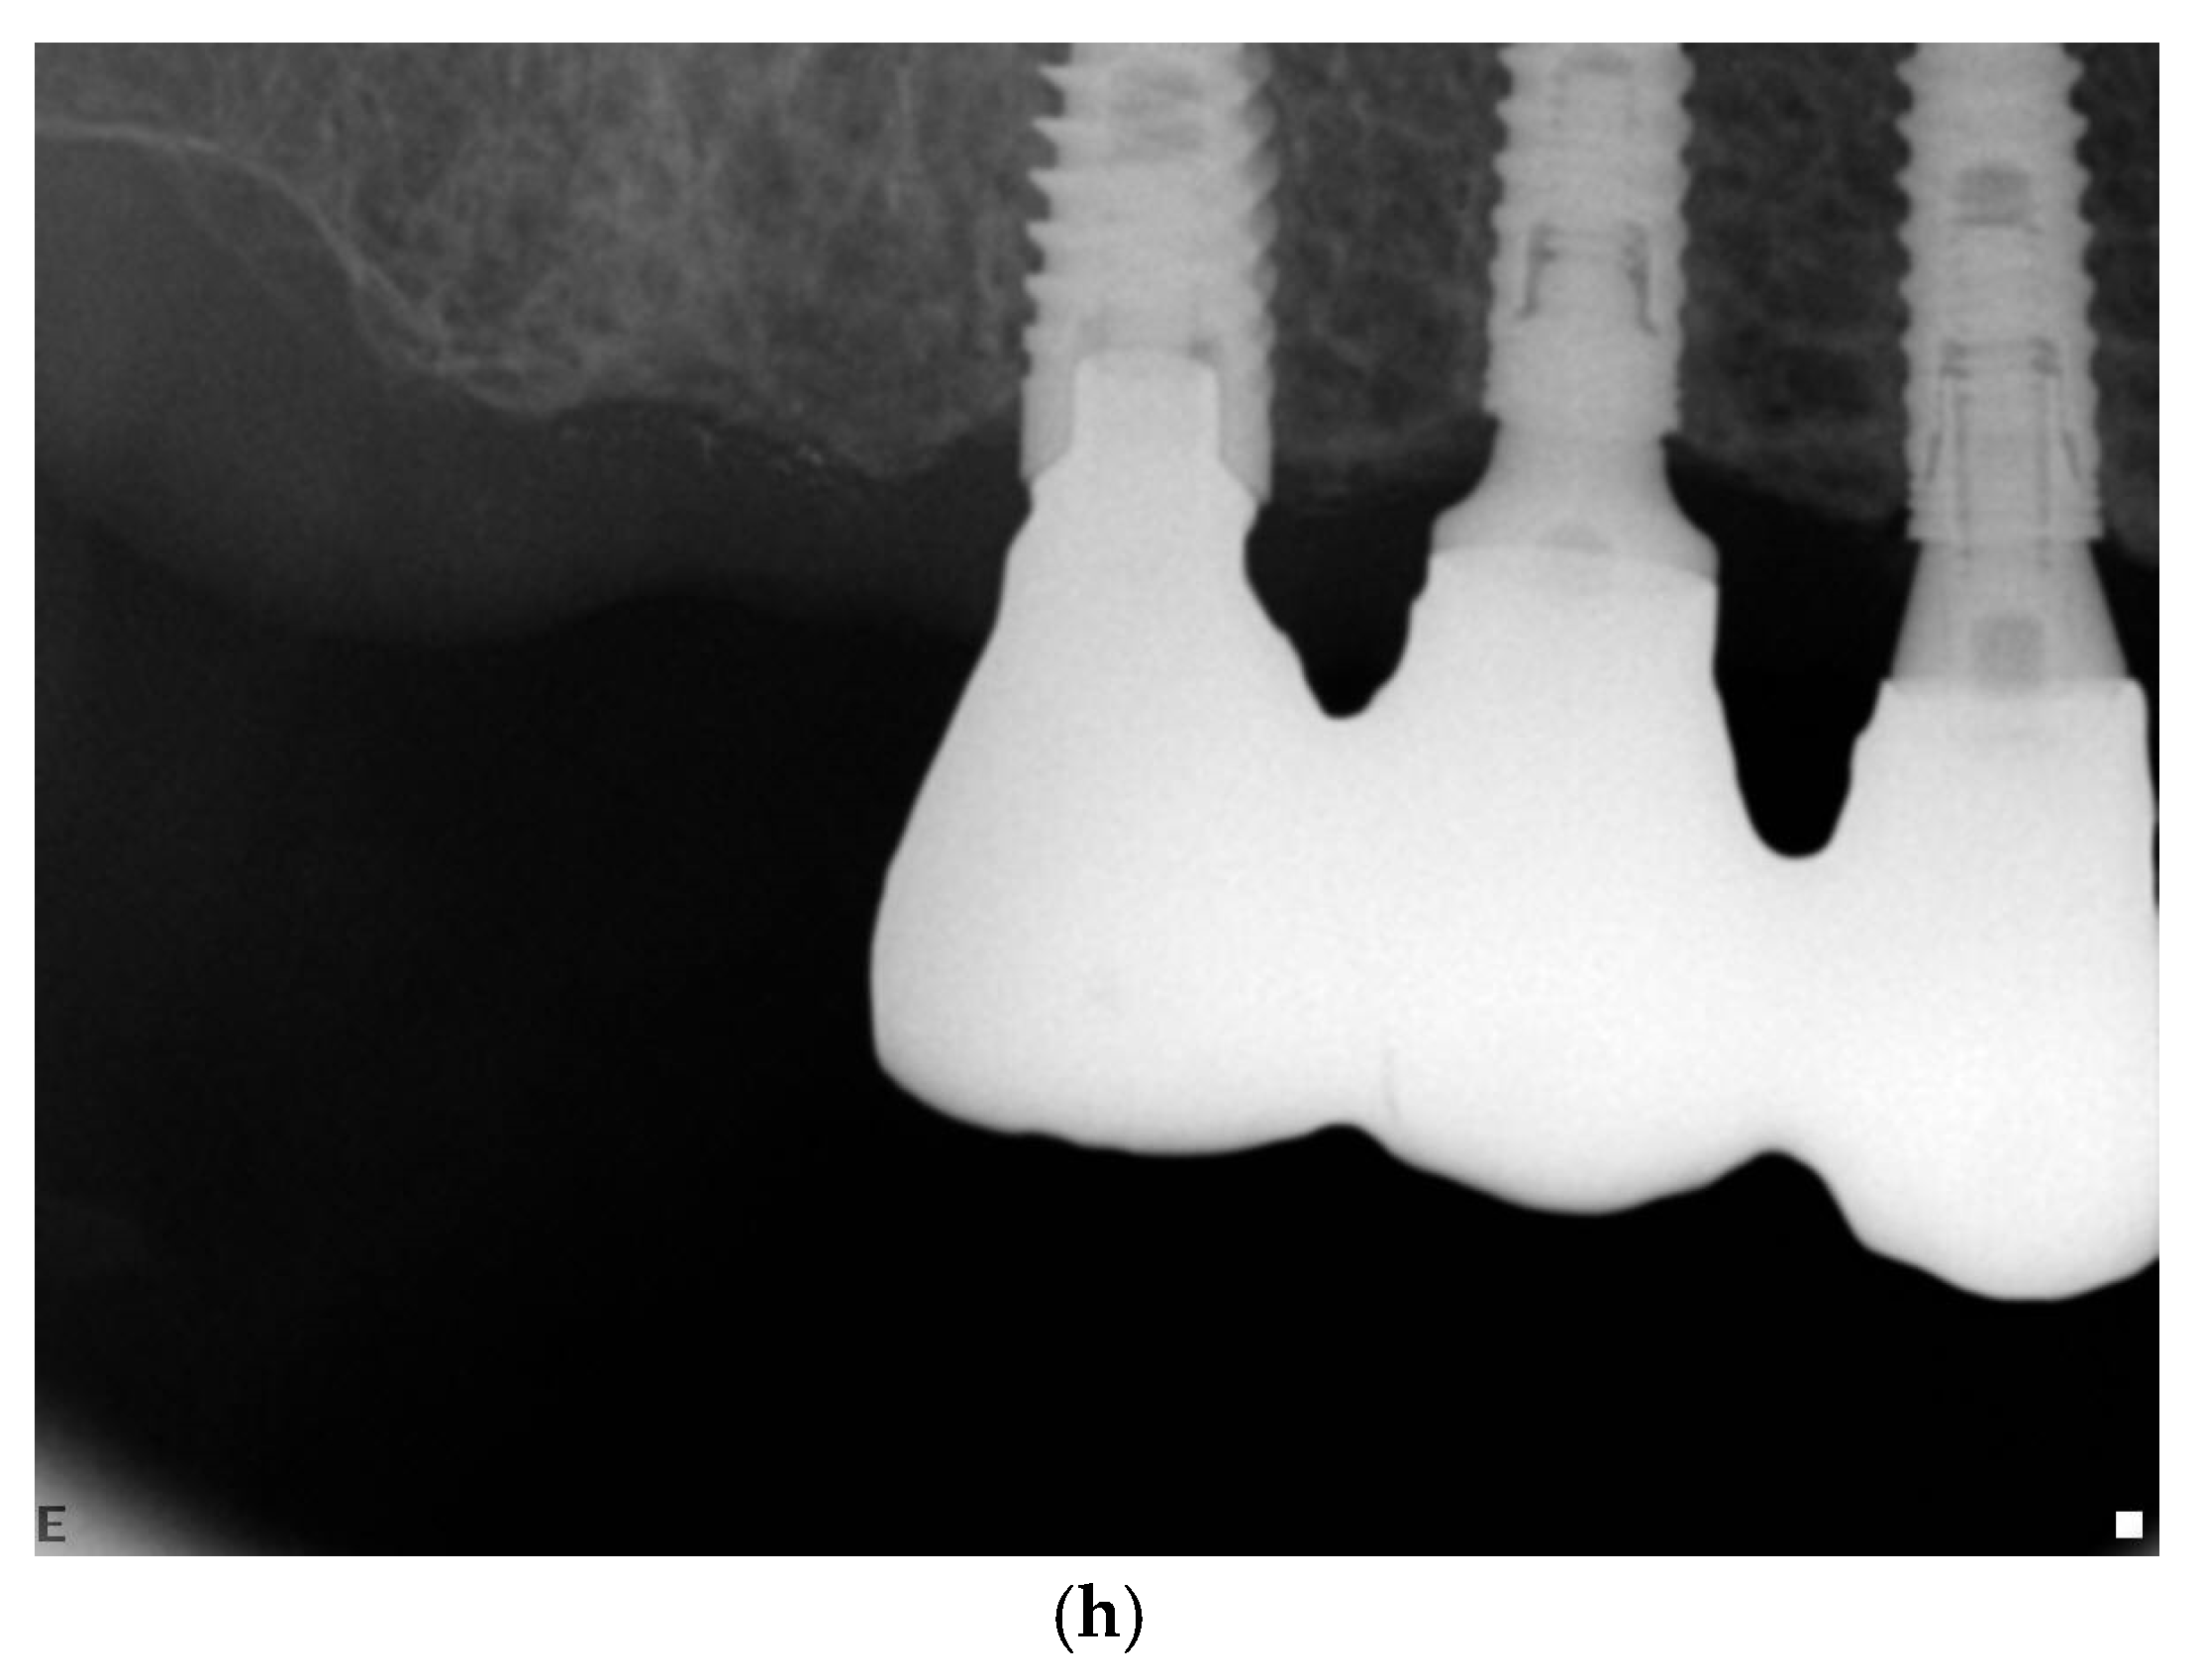

3.5. Radiographic Measurements

5.2. Marginal Bone Level